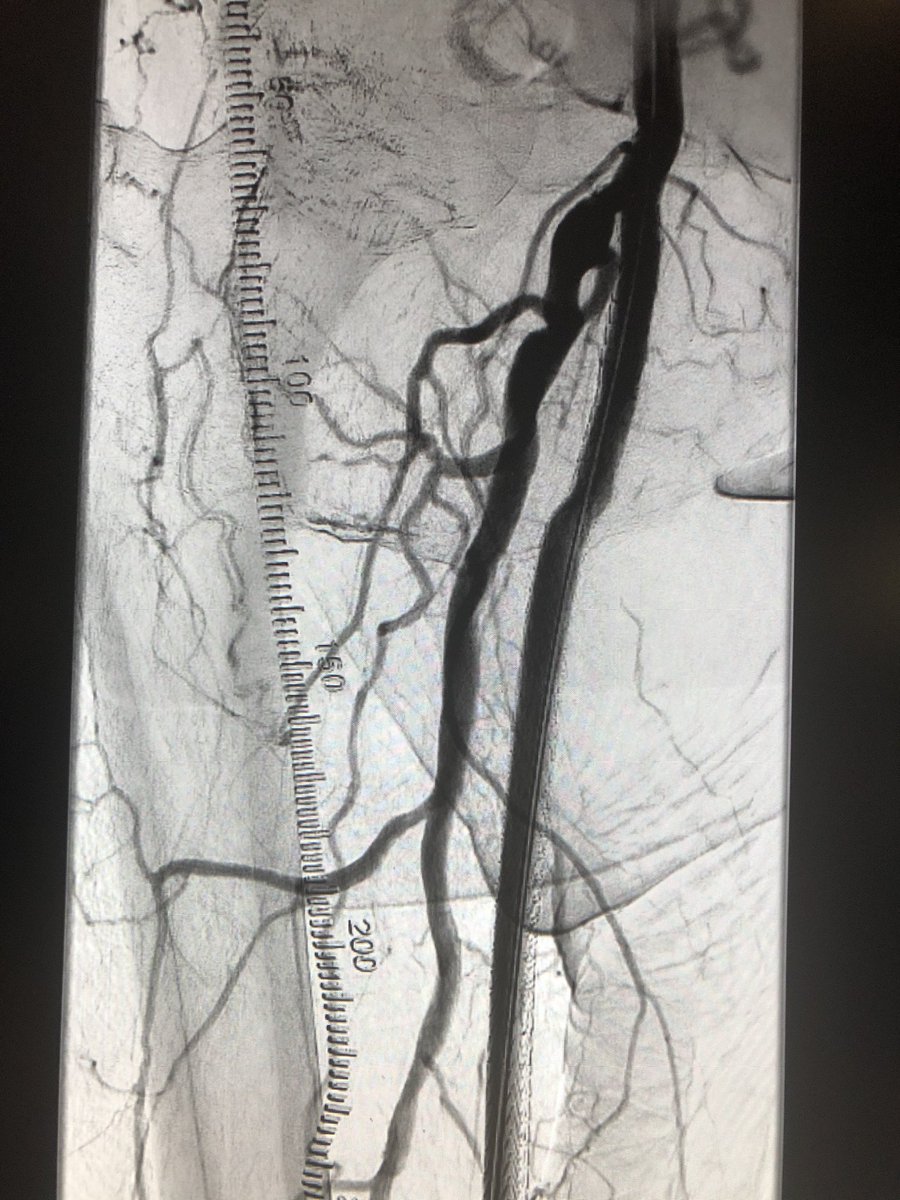

@JChurches @SriniTummala @thegestgroup @SIRspecialists @CAIRweb @TraineesBSIR @SIRRFS @SIR_ECS @VIVAPhysicians @ISETNews @ISEVSonline @BSIR_News @VascularSVS @ACCinTouch @Balt_Group @KyleObradovich @LindsayKThornt1 @bostonsci @MDTVascular @MountSinaiIR Forgot to add @MikePatelMD. Amazing resident. Even better fellow.